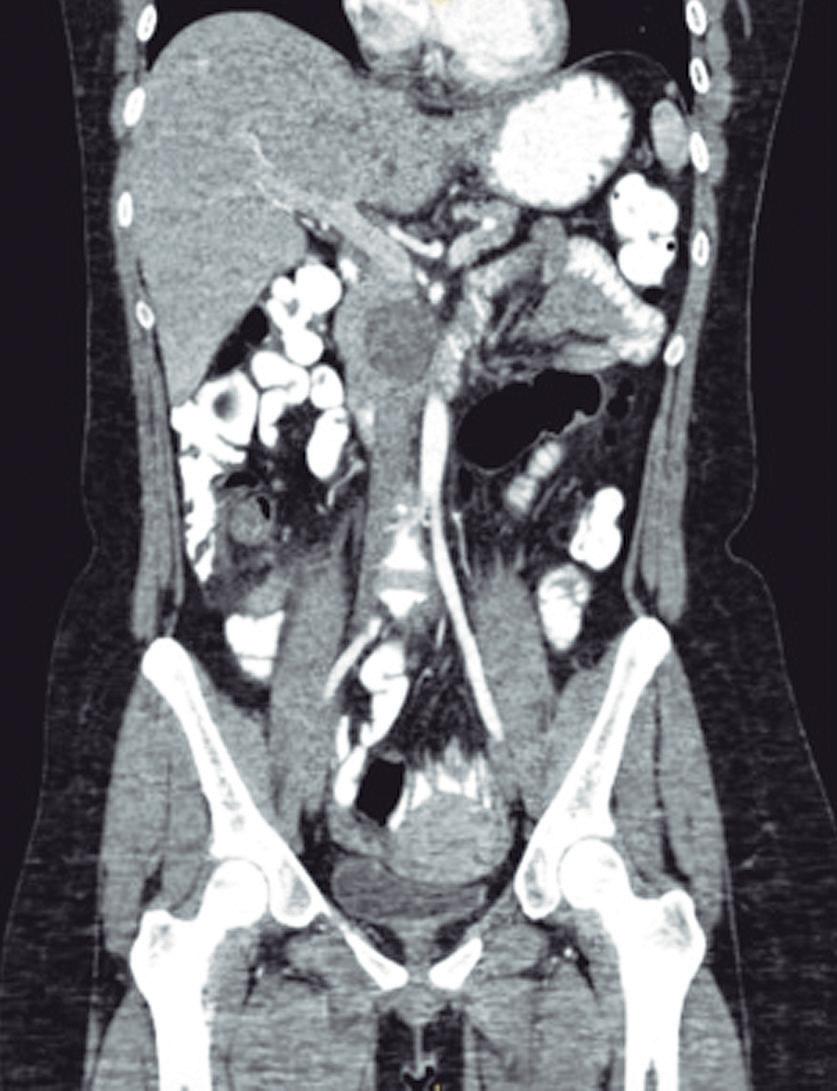

Evaluación de un paciente con dolor epigástrico y hallazgos sincrónicos infrecuentes

Roy López Grove, Daniela Soloaga, Juan Carlos Spina

Roy López Grove, Daniela Soloaga, Juan Carlos Spina 398